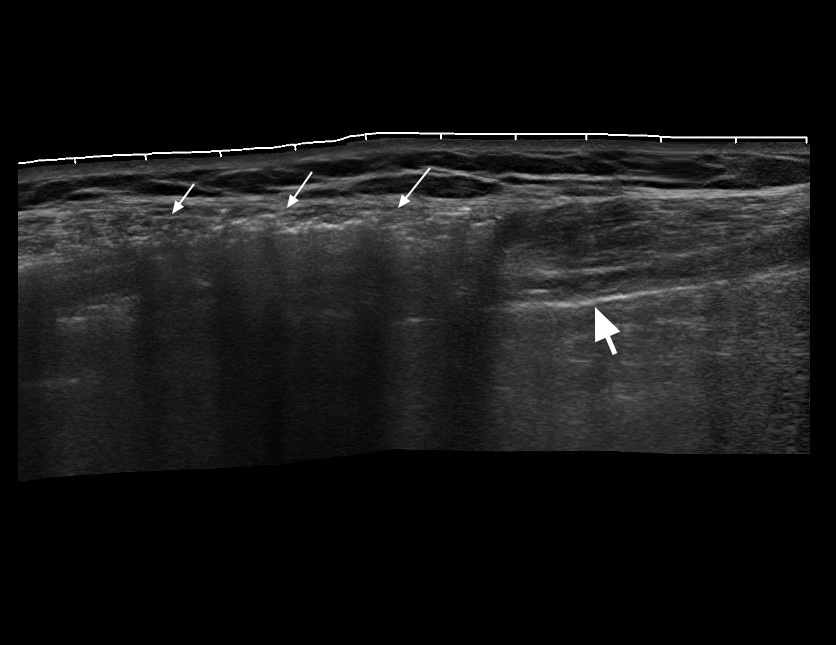

Пальпаторно справа - подкожная крепитация.

Ультразвуковое панорамное изображение и видео подкожной эмфмземы при травме грудной клетки. В подкожно-жировой клетчатке определяется воздух (стрелки). Линия плевры находится глубже воздуха (толстая стрелка). Пальпаторно в зоне скопления воздуха определяется крепитация. Позади воздуха определяются Е-линии. Обратите внимание на подвижность линии легкого и неподвижность "залипшего" в верхней точке грудной клетки воздуха.

Справа во IIм межреберье в плевральной полости определяется небольшое количество свободного воздуха.

Слева воздух не определяется.

Таким образом, УЗИ является довольно чувствительным и информативным методом в диагностике пневматоракса при травме грудной клетки.